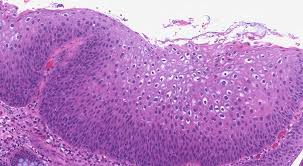

상피내암은 일반적으로 '상피'에서 시작되는 암의 일종으로, 그 세포가 비정상적으로 성장하면서 주변 조직으로 침범하지 않은 상태를 의미합니다. 이는 암의 초기 단계로 간주될 수 있으며, 조기 발견 시 치료가 용이하고 완치 가능성이 높습니다. 상피세포는 우리 몸의 여러 장기와 조직 표면을 덮고 있는 세포들로, 피부와 장기를 보호하는 중요한 역할을 합니다. 상피내암은 이와 같은 상피세포에서 발생하며, 이 세포들이 비정상적으로 변형되어 있습니다.

상피내암의 가장 큰 특징은 주변 조직으로 아직 침범하지 않았다는 점입니다. 이는 암이 진행되는 과정을 이해하는 데 있어 중요한 요소입니다. 초기 단계에서 상피내암은 '전이'라고 하는, 암세포가 다른 신체 부위로 퍼지는 현상이 발생하지 않으므로, 치료 목표가 매우 분명합니다. 상피내암은 다양한 부위에서 발생할 수 있으며, 이에는 유방, 자궁경부, 대장, 폐 등이 포함됩니다. 각 부위에서의 상피내암은 각각의 특성과 치료 방법이 다르므로, 정확한 진단과 적절한 치료가 필요합니다.